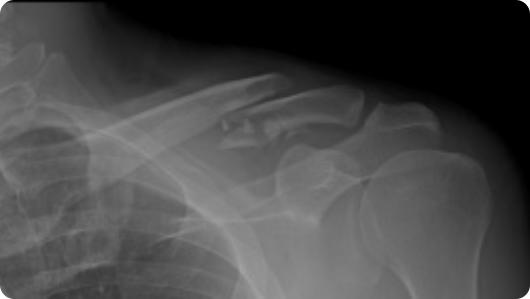

Radiographic image of a clavicle fracture Radiographic image of a clavicle ORIF (plate and screws)

Clavicle Fracture

Clavicle ORIF (Plate and Screws)